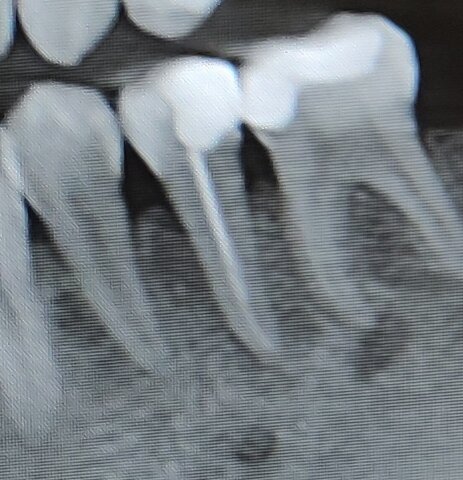

Фото автора. "Пятёрка и шестёрка"

В промежутках между своими походами по врачам, в той же поликлинике я лечила зубы своему сыну у молодого специалиста. Пользуясь случаем, я показываю ей снимок своих зубов и она мне говорит, что это не "пятерка" у меня болит, а корешок рядом стоящей "живой" "шестёрки". И действительно, по снимку видно невооруженным взглядом, что воспаление уже на корешках двух зубов.

Он отправил меня делать снимок обеих челюстей. И выяснилось, что "пятерку" мою нужно перелечивать, т.к. воспаление на корешке. То ли не допломбировал мой профессионал зуб, то ли ещё какая причина, иммунитет мой не выдержал и образовался периодонтит. Закрыть сломанный зуб тоже никак, только ставить имплант. В общем, насчитал мне кругленькую сумму.

Прихожу на приём и первым делом меня просят сделать снимок зуба, как оказалось не спроста. Таким образом, новая врач зафиксировала, что это не она перфорировала зуб.

Из-за того что, основание зуба просверлили, десна вышла наружу и кальцием полечить не представилось возможным, хотя, врач пыталась сделать всё, что могла. Из-за десны видимость ноль и в этом месиве практически вслепую она каким-то чудом запломбировала мне каналы и поставила временную пломбу.